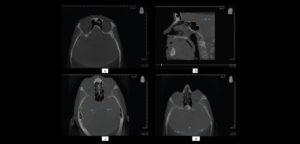

El éxito del tratamiento de las reducciones de fracturas de los huesos del macizo craneofacial así como la disminución de la morbilidad posoperatoria. Para un